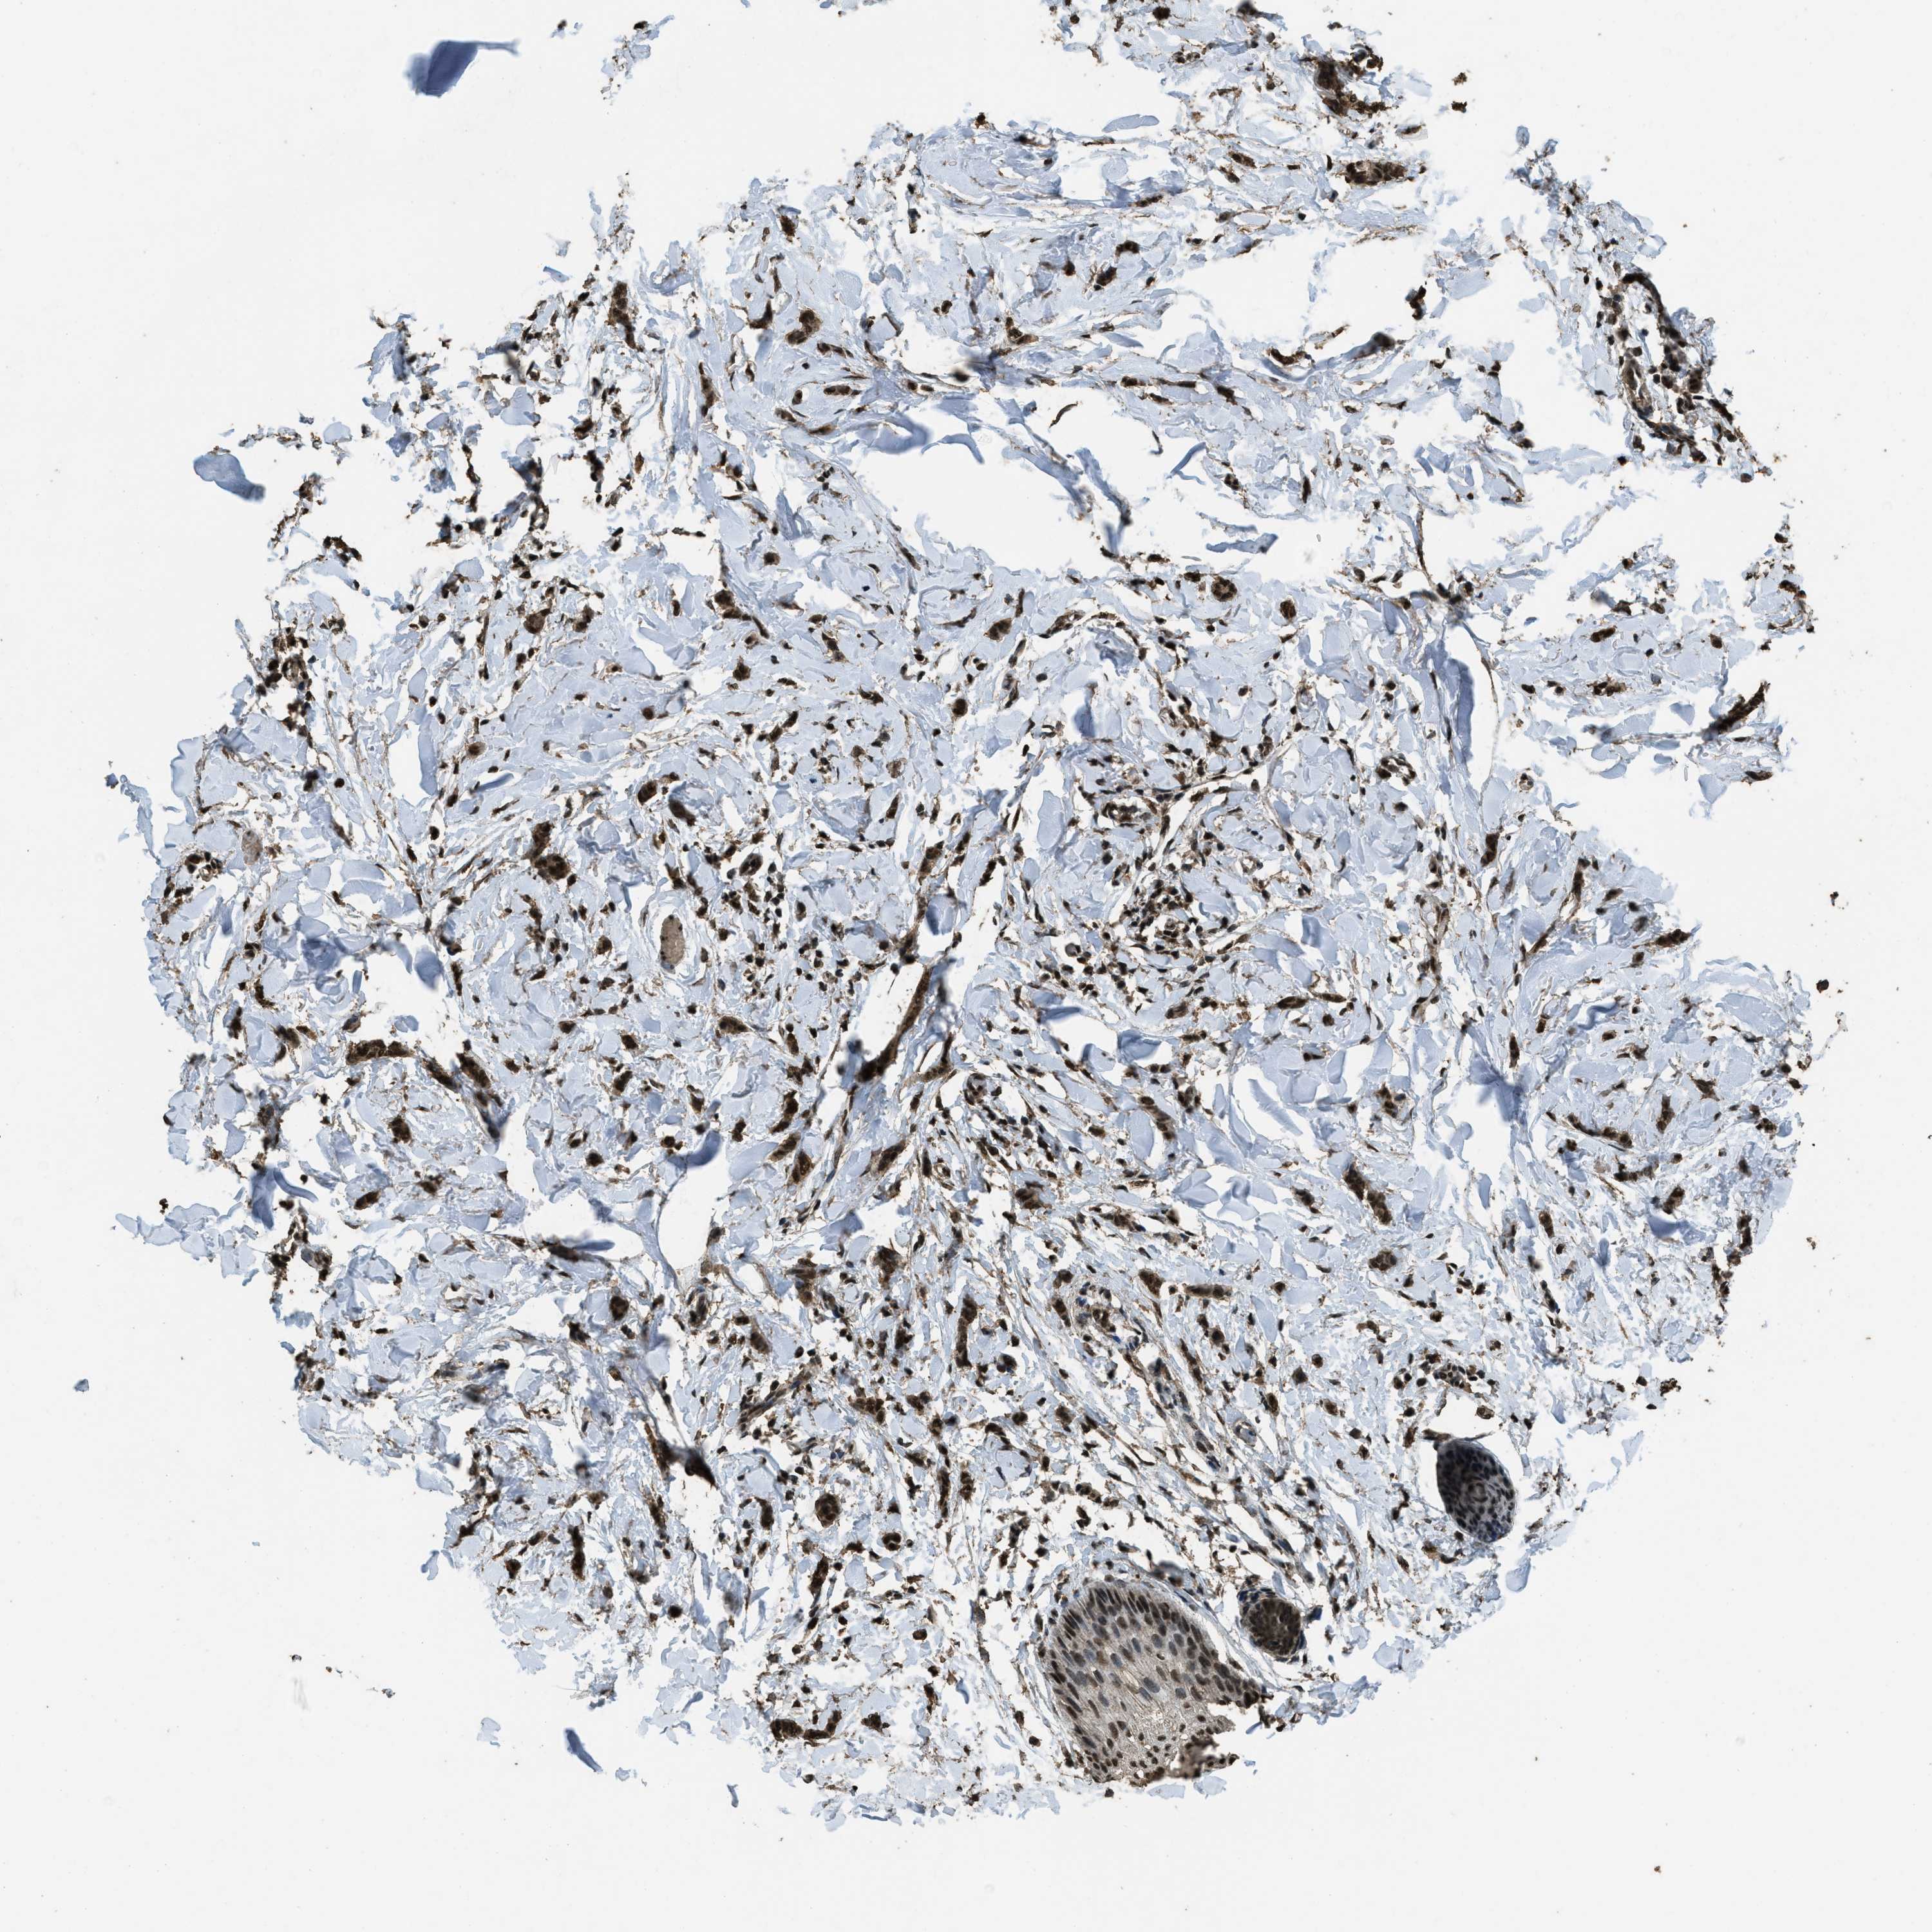

BRCA TCGA BRCA VALIDATION PROTEIN EXPRESSION

ANTIBODIES

AND

VALIDATION